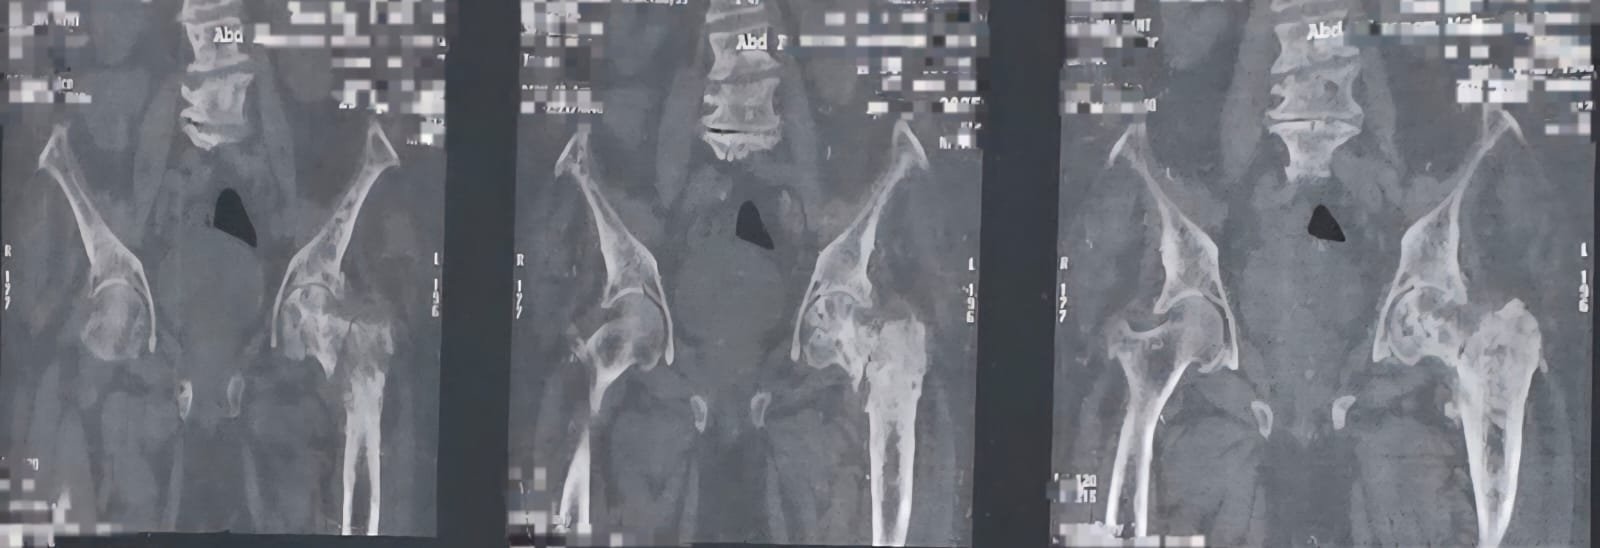

في عمر تجاوز الثمانين، واجه أحد الأبطال تحديًا قاسيًا مع مرض شرس؛ فقد أصيب بسرطان البروستاتا الذي لم يكتفِ بالبقاء في موضعه، بل انتشر في أنحاء متفرقة من الجسم، خاصة العظام، حتى أصاب مفصل الفخذ وتسبب في كسره، مما أفقد المريض القدرة على الحركة.

رغم تعقيد الحالة بسبب انتشار الورم، وضعف عضلة القلب، والأنيميا، وضيق التنفس، قرر الفريق الطبي في مستشفى الزيتون التخصصي خوض التحدي وإجراء عملية تغيير مفصل الفخذ وتركيب مفصل صناعي. وبعد إجراء الفحوصات الدقيقة ومناقشة كافة التفاصيل مع المريض وأسرته، تمت الموافقة بشجاعة وثقة بالله وبالطاقم الطبي.